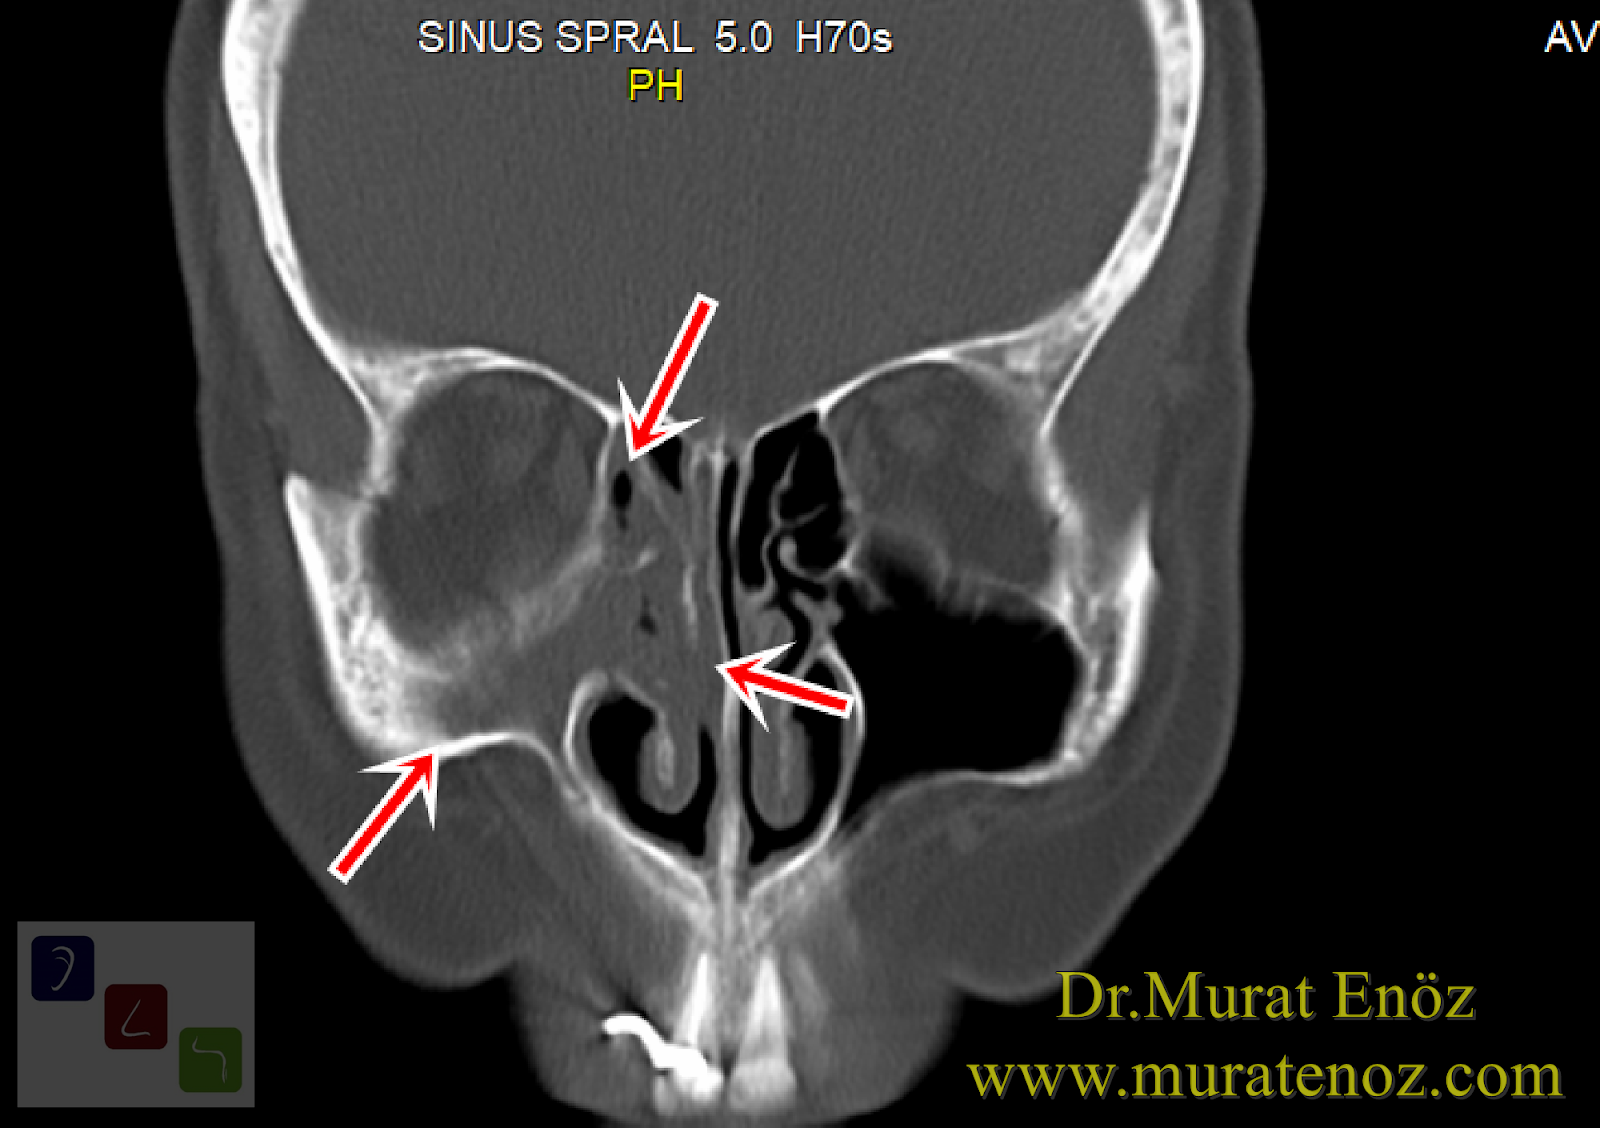

Aşağıdaki paranazal sinüs tomografisi görüntülerinde, uzun süredir yüzünün sağ yarımında baş ağrısı, dolgunluk, burun akıntısı ve basınç hissi tarifleyen hastanın sağ taraftaki maksiller, frontal ve etmoid sinüs boşluklarının sekresyon ve polip nedeniyle kapalı olarak görülmektedir.